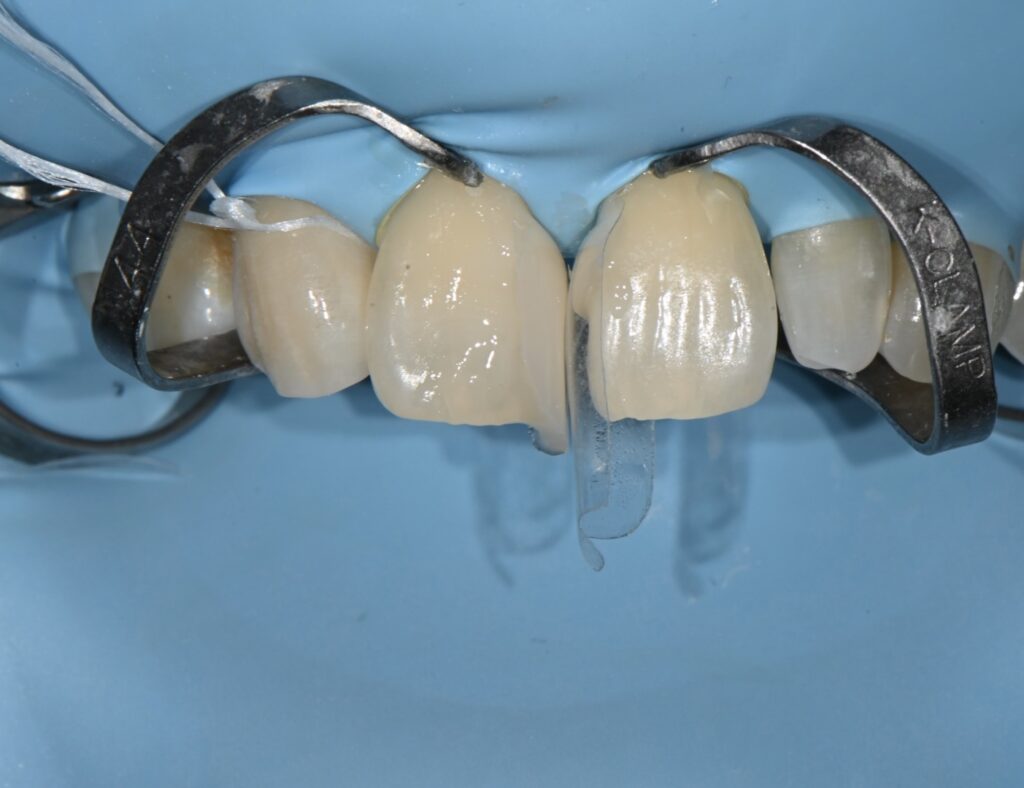

치아 형태를 만들어 주는데요

이 부분은 꼭 알아두셔야 하는 부분이

지금의 형태와 모양이

나중에 1-2주 이후에는 달라질 수 있다는 부분입니다

1차 형태가 완성이 되었습니다

여기까지가 전부가 아니라

피니싱과 폴리싱 치료가 들어가야 하는데요

1차 피니싱과 폴리싱 완료후 모습입니다

완전히 자연스러운 모습입니다만

치경부 즉 치아의 경계 부위의 형태가 조금 걸립니다

하지만 이 부분은 러버댐이 잇몸을 눌러서 생긴 현상이기에

2주후 추가 피니싱을 하기로 하였습니다